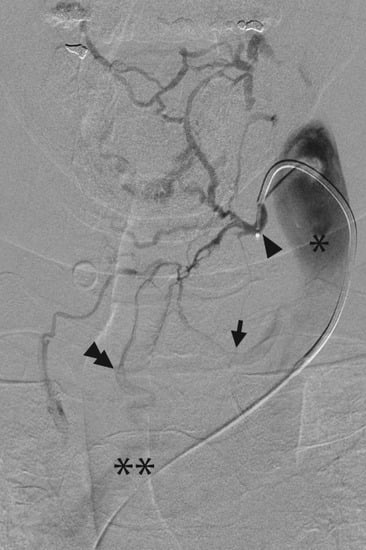

4.2. Adrenal Vein Sampling for Primary Aldosteronism

- Daunt, N. Adrenal vein sampling: How to make it quick, easy, and successful. Radiographics 2005, 25, S143–S158. [Google Scholar] [CrossRef] [PubMed]

- Young, W.F.; Stanson, A.W.; Thompson, G.B.; Grant, C.S.; Farley, D.R.; Van Heerden, J.A. Role for adrenal venous sampling in primary aldosteronism. Surgery 2004, 136, 1227–1235. [Google Scholar] [CrossRef] [PubMed]

- Rossi, G.P.; Auchus, R.J.; Brown, M.; Lenders, J.W.; Naruse, M.; Plouin, P.F.; Satoh, F.; Young, W.F. An Expert Consensus Statement on Use of Adrenal Vein Sampling for the Subtyping of Primary AldosteronismNovelty and Significance. Hypertension 2014, 63, 151–160. [Google Scholar] [CrossRef] [PubMed]

- Makita, K.; Nishimoto, K.; Kiriyama-Kitamoto, K.; Karashima, S.; Seki, T.; Yasuda, M.; Matsui, S.; Omura, M.; Nishikawa, T. A Novel Method: Super-selective Adrenal Venous Sampling. J. Vis. Exp. 2017, 55716. [Google Scholar] [CrossRef] [PubMed]

- Satani, N.; Ota, H.; Seiji, K.; Morimoto, R.; Kudo, M.; Iwakura, Y.; Ono, Y.; Nezu, M.; Omata, K.; Ito, S. Intra-adrenal aldosterone secretion: Segmental adrenal venous sampling for localization. Radiology 2015, 278, 265–274. [Google Scholar] [CrossRef] [PubMed]

- Satoh, F.; Morimoto, R.; Seiji, K.; Satani, N.; Ota, H.; Iwakura, Y.; Ono, Y.; Kudo, M.; Nezu, M.; Omata, K. Is there a role for segmental adrenal venous sampling and adrenal sparing surgery in patients with primary aldosteronism? Eur. J. Endocrinol. 2015, 173, 465–477. [Google Scholar] [CrossRef] [PubMed]